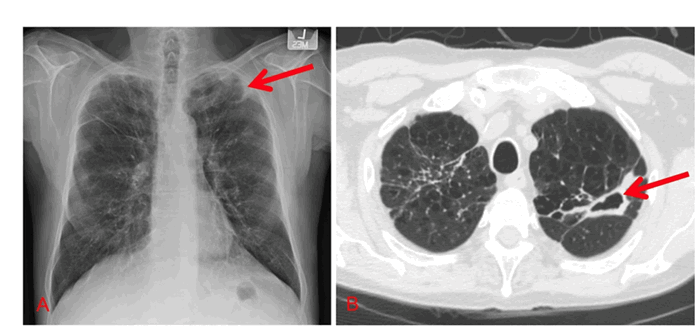

Рентгенодиагностика. При инфицировании НМБ в легких обычно встречаются два рентгенологических паттерна: фиброзно-кавернозная болезнь и узловатая бронхоэктатическая болезнь, или комбинация этих двух рентгенографических картин.

Фиброзно-кавернозная форма обычно возникает у мужчин среднего или пожилого возраста с сопутствующими заболеваниями легких, такими как ХОБЛ или пневмокониоз. Рентгенологическая картина НМБ характеризуется преобладанием поражения верхней доли легкого, полостями с тонкими или толстыми стенками и плевральными утолщениями. В то время как при туберкулезе обычно имеет место кальцифицированная лимфаденопатия и связанные с ней паренхиматозные инфильтраты, которых нет при НМБ инфекции. Тем не менее, рентгенологические данные сами по себе не должны использоваться для дифференциации этих инфекций.

Рентгенограммы пациентов с фиброзно-кавернозным вариантом течения НМБ инфекции.

A. Рентгенограмма грудной клетки, красная стрелка указывает на левостороннюю апикальную тонкостенную полость с окружающей плевральной реакцией. Фоновая архитектура легких имеет увеличенные ретикулярные отметины, соответствующие рубцеванию.

B. Компьютерная томография грудной клетки, аксиальный срез: красная стрелка указывает на толстостенное полостное образование в левой верхней доле. Источник

Злокачественные новообразования легких, грибковые инфекции и легочные васкулиты могут иметь схожие рентгенологические признаки. Поэтому необходима клиническая, рентгенографическая, микробиологическая и, иногда, гистологическая корреляция.